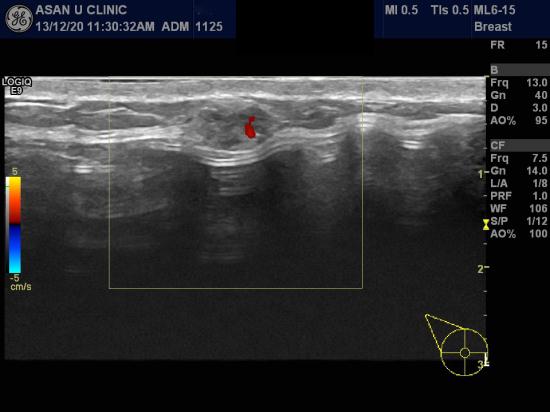

아산유외과 개원 후 47번째 유방암진단.

우측유방에 혹이 조그맣게 만져지기도 하다가 없어지기도 한다는 이유로

본원에 내원하신 39세 여성분입니다.

보형물이 있어 구분이 어렵긴 했으나

0.83cm 미만의 작은 혹이 있었고

모양이 전형적이지 않아 중심핵생검을 시행하였으며

침윤성 유관암으로 진단되셨습니다.

설마했는데,,,,,

유방을 성형한 경우에도 유방암 발생을 피해가진 못합니다.

조기검진이 최선의 치료입니다.